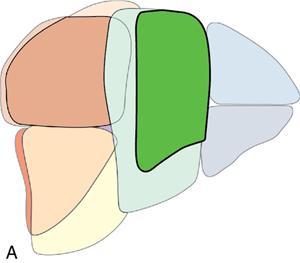

Ritu K. Kashikar, Shrinivas B. Desai Imaging is the mainstay of noninvasive diagnosis of the spectrum of abdominal pathologies or proving absence off thereof. Knowledge of normal anatomy and important normal variants is thus essential for the radiologist in order to avoid misinterpretation or erroneous diagnosis. This chapter highlights the normal anatomy of the hepatobiliary systems including the blood vessel and draining ducts and discusses relevant anatomical variants which may have important clinic implications. The liver is the largest abdominal organ, occupying the right upper abdominal quadrant and is in close approximation with the diaphragm, stomach and the gallbladder. It is largely covered by the costal cartilages. The liver is encapsulated by Glisson’s capsule which is a dense layer of connective tissue. It is covered by peritoneum, except in the regions of gallbladder fossa, fossa for inferior vena cava (IVC), and the bare area. The bare area is the posterocranial aspect of the liver, adjacent to the dorsal body wall, which is not covered by peritoneum. The liver has two surfaces, the convex diaphragmatic surface and a concave visceral surface. The slit in the hepatic hilum is called the porta hepatis and is penetrated by the right and left hepatic ducts (LHDs), hepatic artery and portal vein (PV). The distal portion of the lesser omentum is called the hepatoduodenal ligament and contains the common bile duct (CBD), hepatic artery, PV, nerves of liver and lymphatics. The liver has dual blood supply with hepatic artery providing 25% of hepatic blood and rest by portal vein (Fig. 9.2.1). Five ligaments connect the liver to the undersurface of the diaphragm. These include the falciform, the coronary and two lateral ligaments, all of which are peritoneal folds. The fifth ligament is a fibrous cord-like structure and represents the obliterated umbilical vein. The peritoneum invaginates into the liver parenchyma leading to formation of fissures. There are four normal fissures: fissures for the ligamentum teres, ligamentum venosum and gallbladder and the transverse fissure (Fig. 9.2.2). The liver is organized into microscopic functional units called lobules or acini. A central terminal hepatic venule surrounded by four to six terminal portal triads form a polygonal unit called the hepatic lobule. The terminal portal triad branches line the periphery of the unit. Between the terminal portal triads and the central hepatic venule the hepatocytes are arranged in one cell thick plates, surrounded by sinusoids. The blood flows from the terminal portal triad through sinusoids into terminal hepatic venule. Bile formed within the hepatocytes empties into terminal canaliculi which coalesce into the bile ducts (Fig. 9.2.3). This structure of the functional hepatic unit forms the basis of various functions of the liver. The normal relations of the liver are: The liver can be divided into right, left and caudate lobes. The right and left lobes are separated by the interlobular fissure and is oriented along a line passing through the gallbladder fossa inferiorly and the middle hepatic vein (MHV) superiorly (Fig. 9.2.4). This plane runs from the left of the IVC to the left of the gallbladder fossa and is a called the Cantlie’s line. Use of standardized, segmental anatomy is imperative because it facilitates communication and treatment planning. The segmental anatomy of liver is primarily based on vascular anatomy. The right lobe is divided into anterior and posterior sectors by of the right hepatic vein (RHV). The left lobe is divided into medial and lateraI sectors by an oblique plane connecting the left hepatic vein (LHV) and the falciform ligament. The liver is divided into upper and lower segments at the level of main portal vein (MPV) bifurcation (Fig. 9.2.5). Various systems are used in classification of liver anatomy. These are discussed in Table 9.2.1. The Couinaud’s system is the most commonly used and divides eight sections/segments which are discussed in details below (Table 9.2.2). 1. Segment 1 – Caudate lobe Bounded anteriorly and medially by the fissure for ligamentum venosum (Fig. 9.2.6). 2. Segment 2: Superior segment of the left lateral sector/section Bounded medially by falciform ligament and inferiorly by plane of MPV, also known as the posterior lateral sector (Bismuth, FCAT) (Fig. 9.2.7). 3. Segment 3: Inferior segment of left lateral sector/section Bounded medially by the falciform ligament and superiorly by the plane of the MPV bifurcation, also referred to as lateral anterior sector (Bismuth, FCAT) (Fig. 9.2.8). 4. Segment 4: Left medial sector/section Bounded laterally by falciform ligament and medially by Cantlie’s line (Fig. 9.2.9). 5. Segment 5: Inferior segment of the right anterior sector/section Bounded anteriorly by the gallbladder fossa and posteriorly by the plane of the RHV, superiorly bounded by the plane of MPV bifurcation (Fig. 9.2.10). 6. Segment 6: Inferior segment of the right posterior sector/section Bounded anteriorly by plane of the RHP and superiorly by the plane of the MPV bifurcation (Fig. 9.2.11). 7. Segment 7: Superior segment of the right posterior sector/section Bounded anteriorly by the plane of the RHV and inferiorly by the plane of the MPV bifurcation (Fig. 9.2.12). 8. Segment 8: Superior segment of the right anterior sector/section Bounded anteriorly by the plane of the gallbladder fossa and MHV, posteriorly bounded by the plane of the RHV and inferiorly by the plane of the MPV bifurcation (Fig. 9.2.13). Owing to its broad area of contact with the anterior abdominal wall, the liver is an ideal organ for evaluation with sonography. Ultrasound is commonly used for evaluation of size of the liver. On longitudinal scans obtained through the midhepatic line, if the liver measures 13 cm or less, it is normal in 93% of individuals (Fig. 9.2.14). The size of liver in various planes is discussed in chapter on normograms. When the area of contact between the liver and the anterior border of the right kidney, exceeds below two thirds of the kidney, the liver is considered as enlarged. The normal liver is homogeneous with fine echoes and appears evenly bright. The hepatic veins, PV and fissures interrupt the homogeneity of the liver parenchyma (Fig. 9.2.15). The parenchymal echogenicity may vary depending on the equipment, transducer and gain settings and should be judged by comparison with internal references like right renal cortex, body of the pancreas and PV walls. When compared with the adjacent normal right renal cortex the liver normally appears hyperechoic or isoechoic. The pancreas in a young individual is hypoechoic compared to the liver, and isoechoic in middle aged adults. As age progresses and fatty infiltration of the pancreas occurs, the pancreas appears hyperechoic to the liver. The liver is hypoechoic to the spleen. The normal liver reveals a density of 55–65 HU on nonenhanced scan and should appear homogenous with the exception of hypodensity in the regions of vessels and fissures. The liver parenchymal enhancement is minimal the arterial phase, with increase in density by only approximately 10 HU. This phase is usually to access vascular anatomy and to detect neovascular enhancing lesion like HCC, metastasis. Considering the fact that 75% of heptic venous supply is from the PV, the normal hepatic parenchyma shows maximum enhancement in the portal venous phase. During the venous/delayed phase the hepatic attenuation starts falling (Fig. 9.2.16). The hepatic fissures appear as linear fat containing structures. All the four fissures are well identifies on CT (Figs. 9.2.17–9.2.20). Normal liver should demonstrate uniform T1 signal similar or isointense to the paraspinal muscles and slightly hyper intense to the spleen. No signal drop should be seen on in or opposite phase. On T2W1 images liver appears slightly hyperintense to paraspinal muscles, isointense to pancreas and hypointense to spleen (Fig. 9.2.21). Following administration of extracellular contrast agents the normal liver parenchyma enhances on PV phase similar to that seen on CT. The arterial phase is preserved to determining vascular anatomy, variants and tumoural enhancement. Gadoxetic acid (Eovist) and gadobenate dimeglumine (MultiHance) are hepatobiliary agents showing excretion by the liver. In the case of gadoxetic acid, hepatic excretion is ~50%, which allows imaging in the hepatobiliary phase at ~20 minutes following injection. Gadobenate has only 3%–5% biliary excretion with hepatobiliary phase at approximately 40 minutes (Fig. 9.2.22). This property makes these agents useful in detection of nonhepatocyte containing lesions which appear hypointense to background liver on hepatobiliary phase. Hepatic anatomic variants are relatively common and represent normal interindividual variation of liver morphology. Normal Anatomic Variants Anatomic anomalies Accessory and pseudofissures may be seen in the liver. True accessory fissures result from infolding of the peritoneum usually along the undersurface of the liver and are rare. The inferior accessory fissure is the commonest accessory fissure and divides the posterior segment of the right hepatic lobe into lateral and medial portions. Diaphragmatic slips may cause indentation over the liver surface and are not commonly seen on imaging (Fig. 9.2.23). Leftward extension of the lateral segment of the left hepatic lobe appearing as a crescentic density that wraps around the spleen is referred to as sliver of liver. The left lobe of the liver may exhibit various forms: leaf like; spatular; truncated pyramid/wedge shaped; and a bifid appearance (Fig. 9.2.24). Elongated left lobe may be mimic splenomegaly, perisplenic hypoechoic collections or less commonly tumours. Imaging clues to diagnosis are establishing contiguity with liver and visualization of parenchymal vessels coursing through. The portion of the liver that extends medially from the right lobe between the IVC and fissure for ligamentum venosum is called the caudate lobe. The caudate lobe is divided inferiorly into a lateral caudate process and a medial papillary process. The medial papillary process projects medially towards the pancreatic head and has applied importance (Fig. 9.2.25). Riedel’s lobe is a tongue-like projection from the anterior aspect of the right lobe and the most common accessory lobe of the liver. It is seen most frequently in asthenic women. The reported prevalence of RL, ranges from 3.3% to 14.5% and the prevalence is higher in women than in men. It can be 20 cm or more in length and may extend up to the iliac fossa. It is usually asymptomatic and is discovered incidentally (Fig. 9.2.26). Accessory liver lobes are defined as a supernumerary lobe of normal hepatic parenchyma in continuity with the liver. This is a rare entity and usually occurs as a result of congenital ectopic hepatic tissue, although rarely may occur as a result of trauma or surgery. Various systems are proposed for classification of ALL. Another method of classification has been proposed based on biliary drainage and presence or absence of capsule. Accessory lobes can be readily diagnosed and characterized on CT or magnetic resonance imaging (MRI) done for related or unrelated conditions. CT shows the lesion as a soft–tissue density mass attached to the liver and isodense to the organ. The portal/hepatic venous branches can be seen coursing through it, in contiguity with the liver (Fig. 9.2.27). The coeliac axis trifurcates into common hepatic, splenic and left gastric arteries at the level of T12–L1. The common hepatic artery becomes the proper hepatic artery after origin of the gastro-duodenal artery. The hepatic artery proper ascends anterior to the PV and medial to the CBD and divides in to right and left hepatic artery (LHA). Occasionally the middle hepatic (segment 4) artery arises from hepatic artery proper. The hepatic artery appears as a tubular hypoechoic structure and shows antegrade flow on Doppler (Fig. 9.2.28). Normally the resistive index is low ranging between 0.55 and 0.7. The hepatic artery, its anatomy, branches, course, calibre are best evaluated on arterial phase of dynamic CT (Fig. 9.2.29). This is also the preferred modality prior to hepatobiliary surgical planning. Contrast-enhanced MRI also shows the above details but spatial resolution is lower. Road map of the arterial vascularity of the donor and recipient is a prerequisite for transplant surgery and complex hepatobiliary surgery. Detailed hepatic arterial anatomy and its variations have its significance in liver surgeries and interventional hepatic procedures, relative to the hepatic lobe involved. A classification method was described by Michel et al. in 1955, and is discussed in Table 9.2.3 (Fig. 9.2.30). I: standard anatomy ~60% (range 55%–61%) II: replaced LHA ∼7.5% (range 3%–10%) III: replaced RHA ~10% (range 8%–11 %) IV: replaced RHA and LHA ~1% V: accessory LHA from LGA ~10% (range 8%–11%) VI: accessory RHA from SMA ~5% (range 1.5%–7%) VII: accessory RHA and LHA ~1% VIII: accessory RHA and LHA and replaced LHA or RHA ~2.5% IX: CHA replaced to SMA ~3% (range 2%–4.5%) X: CHA replaced to LGA ~0.5% Other unclassified variants are: The two most common variants are the replaced right hepatic artery (RHA) arising from the SMA (Fig. 9.2.31) and replaced LHA arising from the left gastric artery (Figs. 9.2.32–9.2.34). Segment 4 artery – Middle hepatic artery (MHA) The middle hepatic artery usually arises from the LHA, it may, however, arise from the RHA (Fig. 9.2.35). The knowledge regarding origin of MHA is imperative in transplant surgery. The MHA can arise from RHA in Patients with replaced LHA. In patients with replaced RHA, the MHA arises from LHA (Fig. 9.2.36). Because of the considerable variability of hepatic arterial anatomy, assessment of this anatomy is crucial in the preoperative evaluation of potential living liver donors. Relevance of donor and recipient arterial anatomy is discussed in details in chapter on liver transplant. The relationship between the arterial variant and tumour is important to establish prior to major surgeries. Injuries to aberrant hepatic vessels and secondary ischaemic biliary strictures can be avoided. A replaced RHA has a more posterior course and long length. This variant may be advantageous in patients undergoing right lobar resection. However, there is greater propensity of involvement of replaced RHA by pancreatic head. The radiologist must be vigilant in reporting this variant (Fig. 9.2.37). Accessory RHA can, however, be sacrificed even if encased by neoplasm. An accessory LHA needs to be ligated separately in surgeries where blood supply in the porta hepatis is occluded. Replaced LHA from LGA maybe injured in case of surgeries at the level of hiatus. Hence this variant should be informed to surgeon in patients undergoing gastric surgeries. Preoperative mapping of the hepatic arterial anatomy prior to placement of intraarterial chemotherapy pumps is essential because it helps in deciding whether the candidate is suitable for the procedure and also if technical modifications are needed. The intraarterial infusion pump should be placed in the dominant hepatic artery as proximal as possible, but beyond GDA origin. Inpatients with standard anatomy, the pump is usually placed in the hepatic artery prior just after GDA origin. The location of pump can be modified in patients with variant anatomy, based on origin of GDA and dominant hepatic vessel. The PV is the main vessel in the portal venous system and drains blood from the gastrointestinal tract and spleen to the liver.